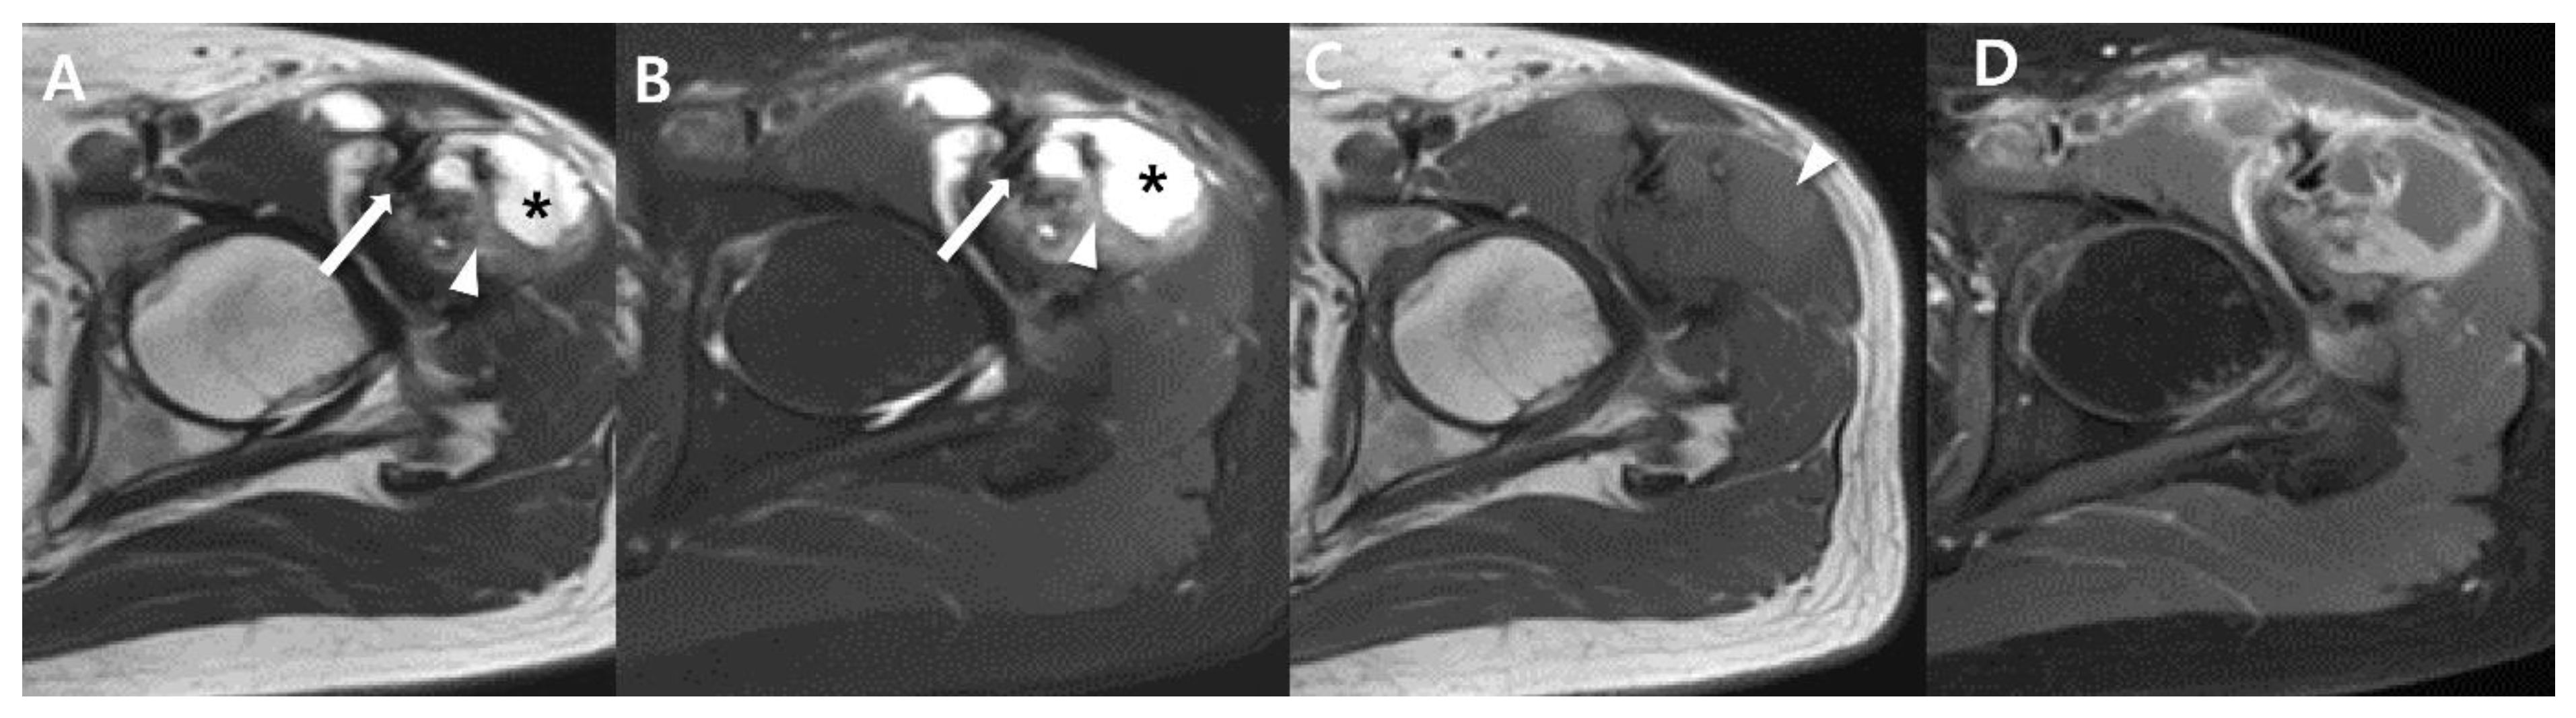

2.4. Magnetic Resonance Imaging (MRI)

2.5. Advanced MRI

4. Prognostic Imaging Features of Synovial Sarcoma in the Extremity

| Imaging features | Intratumoral hemorrhage (fluid-fluid levels) | Poor |

| Triple sign on MRI | ||

| Bowl-of-grapes appearance on MRI | ||